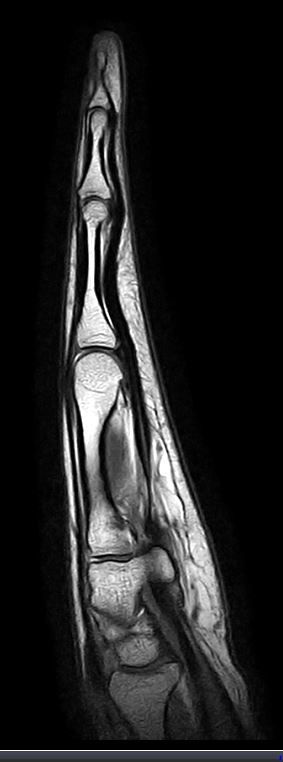

2주전 좌측 3,4수지 손가락이 바깥쪽으로 꺽였습니다.(CT&MRI 사진첨부 했습니다.)

증상은 좌측 제3수지 중지골에 피멍과 통증 그리고 손가락이 안으로 안굽혀 집니다.

골절인지 인대파열인지 아니면 다른 부분이 혹시 보이는지 알려주시면 감사하겠습니다.

• 2번 째 사진